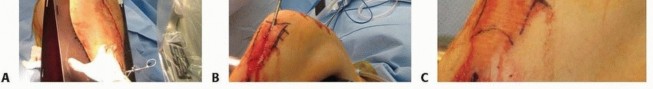

** Surgical Approach ### Medial Parapatellar Tendon Approach Palpate and mark the medial border of the patellar tendon ( TECH FIG 1, line A). Incise the skin at the medial border of the patellar tendon. Full-thickness skin flaps are developed. Dissection is carried down to the retinaculum. The retinaculum is then split, and the patellar tendon is retracted laterally. Do not incise the capsule. ### Transpatellar Tendon Approach Palpate and mark the medial and lateral border of the patellar tendon, the inferior border of the patella, and the tibial tubercle ( TECH FIG 1, line B). Incise the skin starting at the inferior margin of the patella and continue distally in the middle of the patellar tendon. Full-thickness skin flaps are developed. Incise the paratenon in the midline, and elevate medial and lateral flaps to identify the margins of the patellar tendon. Make a single full-thickness incision in the midline of the patellar tendon. Do not incise the capsule and avoid injuring the menisci at the inferior margin of the incision. ### Lateral Parapatellar Tendon Approach Palpate and mark the lateral border of the patellar tendon ( TECH FIG 1, line C). Incise the skin at the lateral border of the patellar tendon. Full-thickness skin flaps are developed. Dissection is carried down to the retinaculum. The retinaculum is then split, and the patellar tendon is retracted medially. Do not incise the capsule. ### Semiextended Position 26 Medial Parapatellar Approach Either a standard midline or limited medial skin incision can be used ( TECH FIG 2). Full-thickness skin flaps are developed. The distal portion of the quadriceps tendon is incised, leaving a 2-mm cuff of tendon medially for later repair. A formal medial arthrotomy is done extending around the patella, leaving a 2-mm cuff of capsule and retinaculum for later repair, and continuing along the medial border of the patellar tendon.

### TECH FIG 2 • A. A formal full medial parapatellar approach allows for easy patellar subluxation and start site localization but requires significant dissection. B. The alternative is a limited medial approach. (B: Courtesy of Paul Tornetta III, MD.) Suprapatellar Approach 28 The suprapatellar approach requires special nail insertion instrumentation as well as cannulas for guide pin placement and reaming. The skin incision is made at the superomedial edge of the patella ( TECH FIG 3). Full-thickness skin flaps are developed. Make a superomedial arthrotomy large enough to place the special instrumentation. An alternative skin incision can be made extending from the midline of the superior pole of the patella proximally (see TECH FIG 1, line E). Full-thickness skin flaps are developed. Incise the quadriceps tendon in the midline, extending proximally from the superior pole of the patella, and make an arthrotomy. Mobilize the patella and free up any adhesions in the patellofemoral joint. ### Extra-articular Extended 14 Semiextended nailing is performed with the goal of remaining outside knee synovium/joint. Medial or lateral parapatellar approach is selected based on patellar laxity. A curvilinear incision begins at the medial border of the proximal third of the patellar tendon and extends proximally 554** to the medial border of the patella and then to the level of the proximal pole.